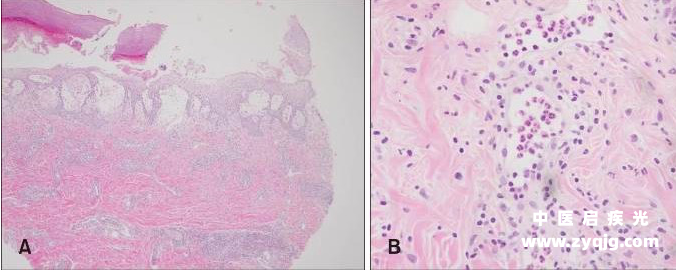

检查发现轻度乳头状真皮水肿,致密、弥漫性间质性皮炎,中性粒细胞占优势。革兰染色、高碘酸-希夫染色、淀粉酶、抗酸杆菌染色均没有发现微生物。皮肤活检标本与阴性组织培养的分析结果最符合急性中性粒细胞性皮肤病(Sweet 综合征)

1.png

皮肤活检结果

图片来源:PubMed [3]